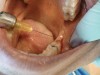

After the initial pass with the laser, the inflamed gingiva bled slightly and the surgeon defocused the beam by increasing the nozzle-to-tissue distance to quickly obtain hemostasis (Figure 6). Note the excellent visualization and the clear operatory field.

Fig 6. Excellent hemostasis after the completed ablation of the inflamed gingiva.

Figure 6